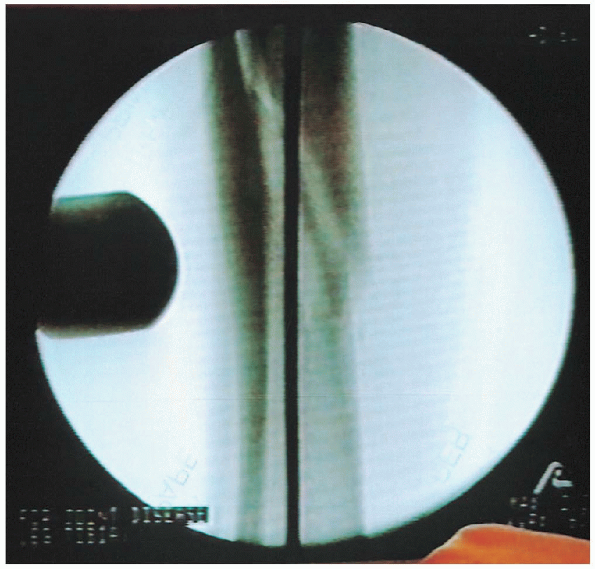

Proximal and distal locking screws are inserted from medial to lateral

in the subcutaneous border of the tibia. The freehand technique

requires targeting of the skin incision. The image intensifier is lined

up with the nail and tilted and rotated until a perfectly round hole is

visualized. It is helpful to move the C-arm head away from the tibia to increase the working space and aid in magnification of the hole.

The sharp point of the trocar-tipped pin is placed on the skin until it

is centered in the hole. A 1-cm stab wound is made directly over the

hole on the medial aspect of the tibia. The sharp, pointed pin is again

placed on the bone until it is centered in the hole. It is brought into

the longitudinal axis and checked with fluoroscopy to ensure that it is

centered in all planes. The pin is then passed into the tibia.

Fluoroscopy is used to verify that the pin has corrected targeted the

nail and the pin drilled through the far cortex. The length for the

locking is determined using a second pin of the same length or a depth

gauge, or it is estimated using the image intensifier. The screw is

then inserted. The screw should be 5 mm too long, because this makes removal of a broken screw easier.

A lateral radiograph should be checked again to be absolutely certain

the screw is in the nail and has not moved anteriorly or posteriorly.

FIGURE 37-20. A freehand technique is used to insert the distal locking screws. A: The image intensifier is lined up with the nail and tilted and rotated until a perfectly round hole is visualized. B: The sharp point of the trocar-tipped pin is placed on the skin until it is centered in the hole. C: The pin is then brought into the longitudinal axis and passed into the tibia. D: Fluoroscopy is used to verify that the pin has correctly targeted the nail and that the pin drilled through the far cortex. E: